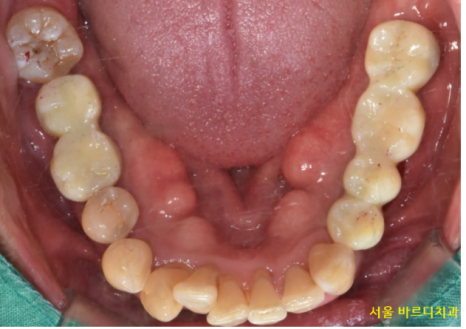

231218

그동안 치아 상태는 이런 모습이셨어요.

어금니라고는 단 2개 만 남아있었습니다.

오른쪽 1개 왼쪽 1개

식사가 얼마나 어려우셨겠어요~

뭐라도 드셔야 하시니 임시틀니로

식사하실 수 있게 도와드렸습니다.